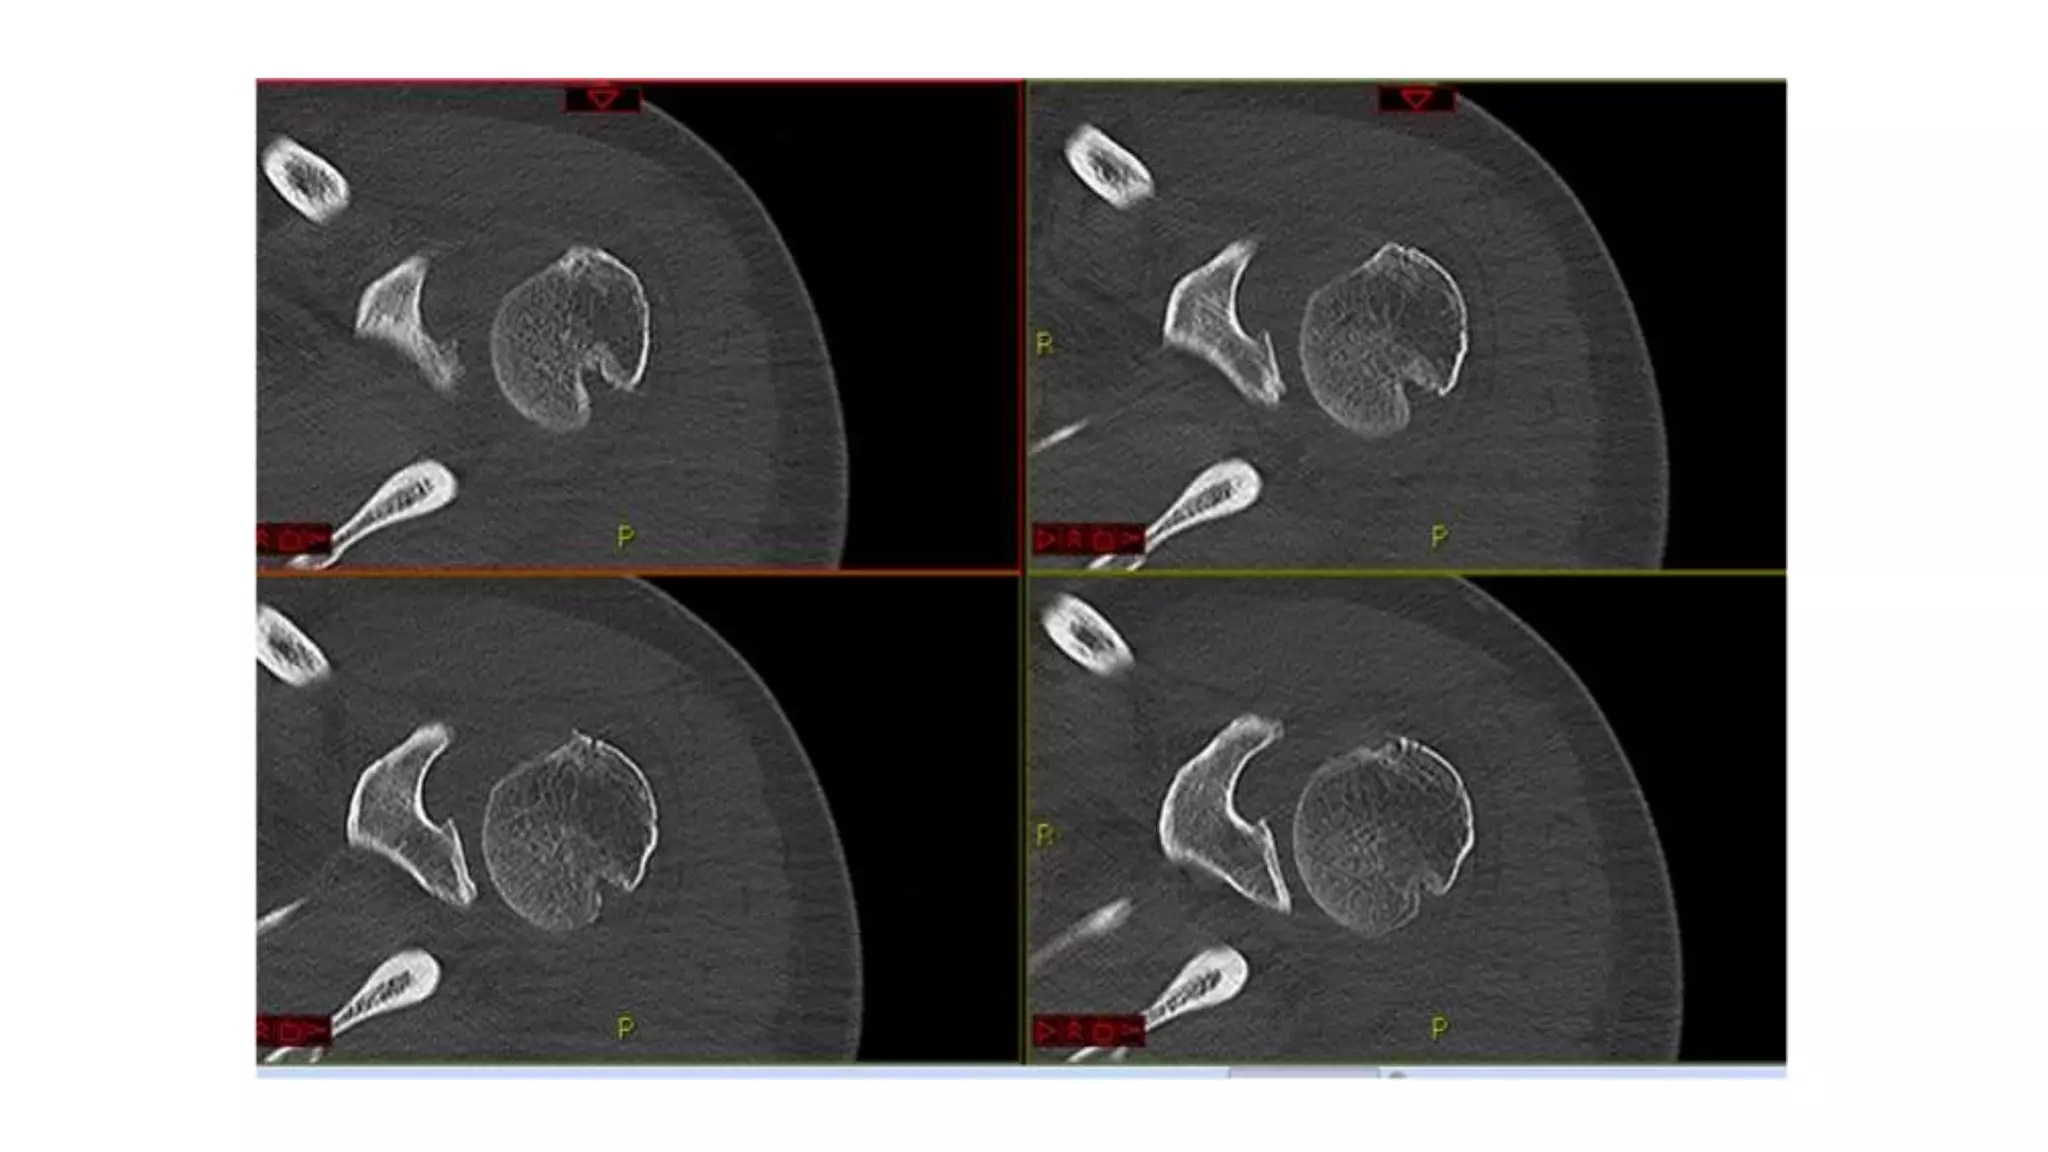

• CT scan

• helpful for evaluation of bony injuries

Imaging Radiographs • true AP •scapular Y • axillary other helpful views • West Point view :- shows glenoid bone loss • Stryker view :- shows Hill-Sachs lesion • CT scan • helpful for evaluation of bony injuries • MRI • best for visualization of labral tear • addition of intraarticular contrast • increases sensitivity and specificity